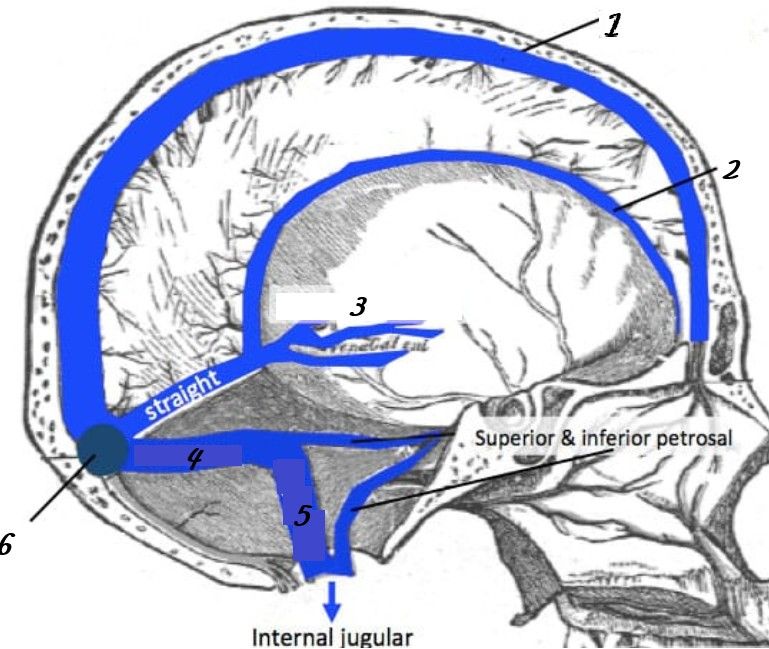

Superior sagittal sinus

Inferior sagittal sinus

Straight sinus

Transverse sinuses

Sigmoid sinuses

Superior sagittal sinus: runs in falx cerebri → drains to confluence of sinuses (1)

Inferior sagittal sinus: joins great cerebral vein → forms straight sinus (1)

Straight sinus: drains to confluence (1)

Transverse sinuses: from confluence → become sigmoid sinuses (1)

Sigmoid sinuses: drain into internal jugular vein (1)

Confluence of sinuses = meeting point (superior sagittal, straight, occipital)

Internal jugular vein is final drainage pathway